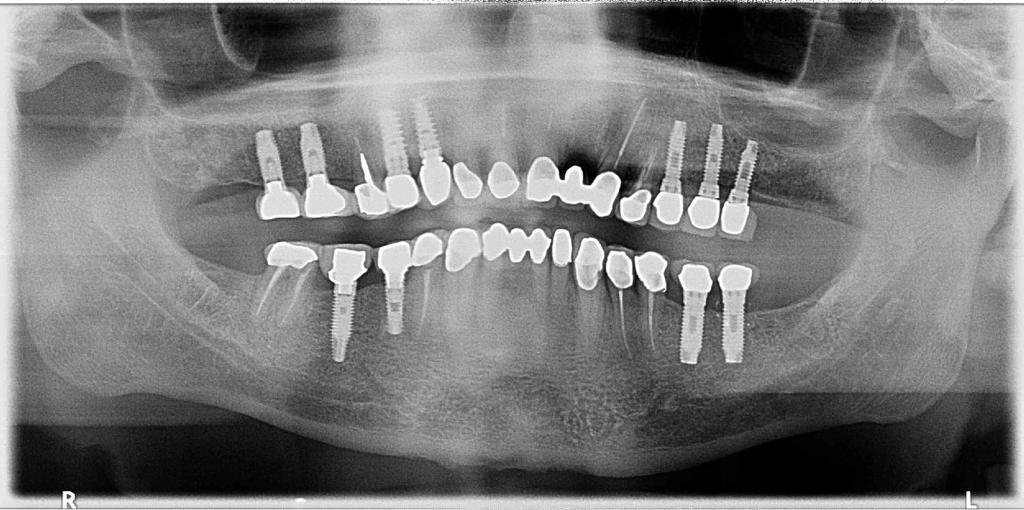

Buenas, podríais ayudarme con la marca, modelo y medidas de los implantes que lleva el paciente en boca. Cualquier ayuda es válida, muchas gracias!!

Paciente acude con implante en posición de 16. No conoce el nombre de la casa comercial. Agradecería ayuda para identificarlo y poder rehabilitar dicho implante. Muchas gracias